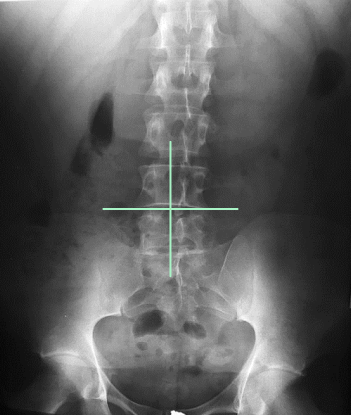

AP L-Spine: Eval Criteria

Centered at the crest (or 1.5” above) to include T12 to sacrum

No rotation

Open intervertebral joint spaces

How does rotation manifest on an AP L-spine?

SI joints unequal from spinous processes

Spinous processes shifted to either side of midline of vertebral column

Transverse processes of unequal length

AP L-Spine: Is this Image Good?

No.

Slight right rotation evidenced by spinous processes projected to the left of midline

T12 is clipped due to low centering at the crest

Needs collimation

Needs marker